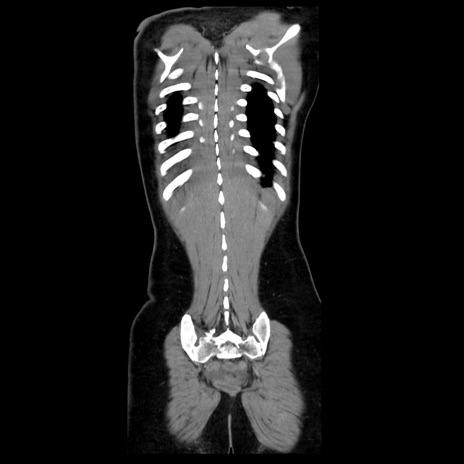

症例39(冠状断像)

【症例】40歳代女性

【主訴】上下腹部痛

【現病歴】2日目から下腹部痛あり。夜間は痛みで眠れなかった。昨日より上腹部痛と下痢が出現。臥位で痛みは軽快したため、休んでいた。本日になって臥位でも立位でも痛みが強くなってきたため救急要請。

【既往歴】子宮内膜症

【身体所見】部:平坦・軟、左上下腹部に圧痛あり、反跳痛あり。

【データ】WBC 21800、CRP 26.78

CT